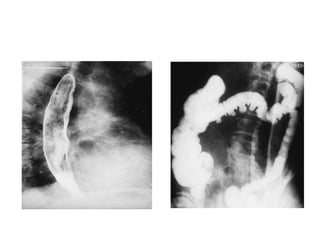

2. oesophagus: is involved in approximately 75% of all patients and is the most

• typical radiological appearance is that of an atonic dilated oesophagus, which

contains air in the resting state

• Stricture of the lower end of the oesophagus occurs in just over 10% of patients

• Hiatus hernia occurs in approximately 25% of patients

• most striking radiological change is the presence of wide-mouthed diverticula, best

demonstrated on post-evacuation roentgenograms